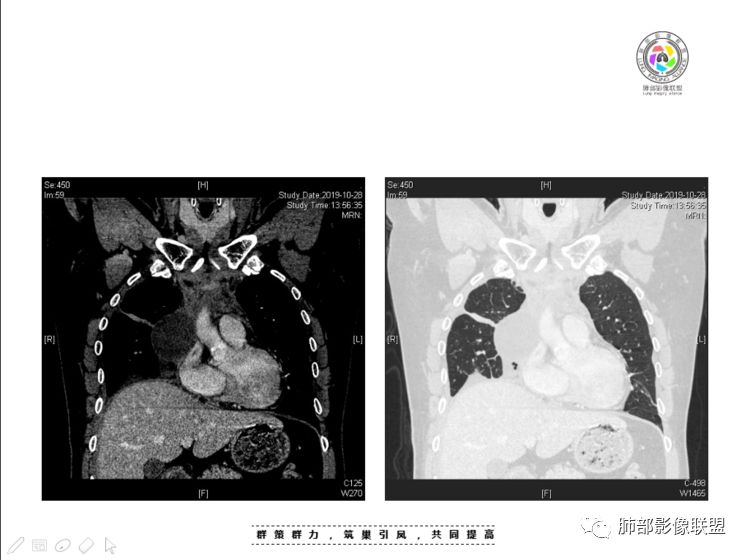

我认为囊张力高,积液中的气体均在周围,外侧、下方,囊内有间隔:各腔密度不一致;提示:囊腔属于前纵隔,不是包裹性积液;现在的问题:囊腔与内侧的病灶是否是一体的

2、前纵隔内病灶囊实性混杂密度病灶,囊性病灶主要位于右侧,张力较高,有分隔影,囊壁右侧缘光整,病灶左侧实性部分边界不清明显强化,病灶肺瘤交界面大部分边界清楚,部分模糊。

胸腺瘤/胸腺癌:病灶内那么大的囊,常规考虑B型以上胸腺瘤,囊内有分隔影,病灶周围脂肪间隙模糊,常规考虑侵袭性胸腺瘤或胸腺癌,若侵袭性胸腺瘤,常侵犯胸膜、心包,很少累及肺。胸腺癌易侵犯胸膜、肺并纵隔淋巴结及远处转移。但肺内腺癌形态更符合原发灶。胸膜及叶间裂转移则即可来自肺,也可来自胸腺癌。

尽管前纵隔病灶缺乏相关病理资料,但是小编还是认为肺内与纵隔病灶以二元论解释。只是肺内恶性病灶引发的胸膜改变可能会影响我们对纵隔病灶的判断。